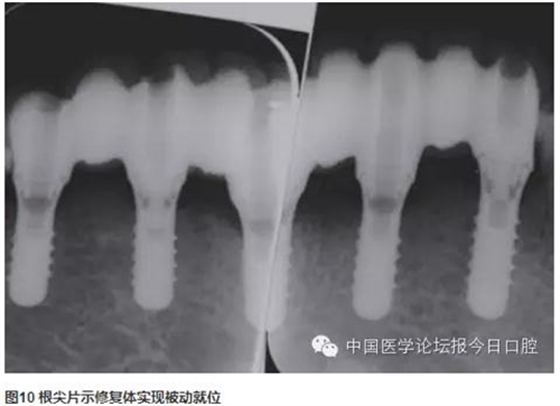

技工室制作純鈦支架,聚合瓷修復牙齒和牙齦形態(tài),患者口內(nèi)試戴,只將一個種植體的固定螺絲加力,拍片可見其余3顆種植體均實現(xiàn)被動就位,然后將4顆種植體固定螺絲加力,封口(圖2~圖10)。

曲面體層片示:種植體基臺與修復體密合性良好。1年后復診,支架無松動、折斷,中央螺絲未見折斷、松動,修復體未見崩瓷。種植體無松動,種植體周圍少量軟垢存,黏膜未見紅腫。種植體周圍探診深度:下頜左側(cè)尖牙(近中2mm、頰側(cè)3mm、遠中4mm、舌側(cè)2mm),下頜左側(cè)中切牙(近中2mm、頰側(cè)2mm、遠中4mm、舌側(cè)2mm),下頜右側(cè)側(cè)切牙(近中2mm、頰側(cè)2mm、遠中3mm、舌側(cè)3mm),下頜右側(cè)第一前磨牙(近中3mm、頰側(cè)2mm、遠中4mm、舌側(cè)3mm)(圖11~圖13)。